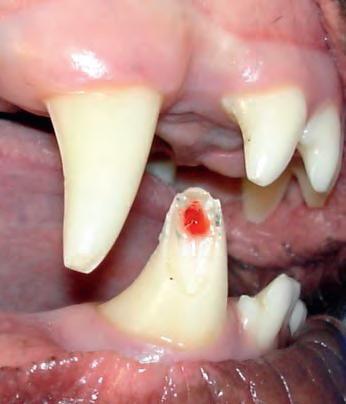

B) Gecompliceerde fractuur: niets doen is geen optie Bij een gecompliceerde fractuur ligt het wortelkanaal open. Als de fractuur net ontstaan is, zal er bloed zichtbaar is. Dit is een pijnlijke situatie voor de hond, aangezien niet alleen de bloedvaten, maar ook de zenuwen in het wortelkanaal bloot komen te liggen. Na verloop van tijd zal het wortelkanaal geïnfecteerd raken door bacteriën vanuit de mondholte.

Wat zijn de behandelmogelijkheden bij een gecompliceerde breuk? Niets doen is in mijn ogen geen optie, aangezien een

open wortelkanaal altijd zal leiden tot een abces bij de wortelpunt in het kaakbot. Dit zorgt voor veel ongemak bij de hond en een continue infectie in de kaak. Als voorbeeld toon ik enkele foto’s van een patiënt die al enige tijd rondliep met een gecompliceerde fractuur van de knipkies in de bovenkaak.